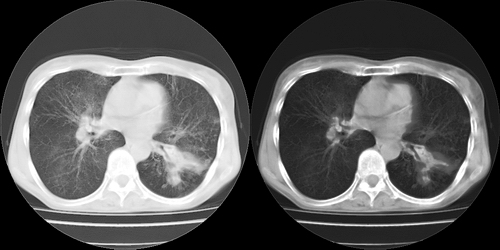

以下是引用lihuuuu在2006-7-18 18:16:00的发言:[br]支持肺结核诊断[br]本病例符合结核“三多”“三少”特征(多病灶、多形态、多钙化、少肿块、少堆积、少增强)中的前五个特征,另外左下叶背段有不张样改变-考虑伴有支气管内膜结核所致段不张。

以下是引用yang4132在2006-7-18 10:04:00的发言:[br]两肺多发 多形态病变,部分半纤维条索和斑点壮钙化,胸膜肥厚粘连,考虑结核。